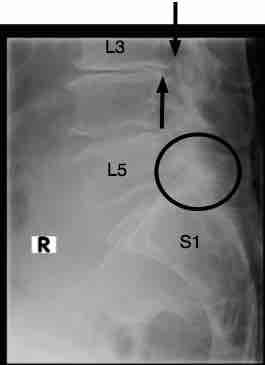

X-rays and an MRI are now imperative to make the diagnosis; what you describe sounds like lumbar spinal stenosis, but that's speculative, and until an accurate diagnosis is made, it's difficult to recommend any course of action.